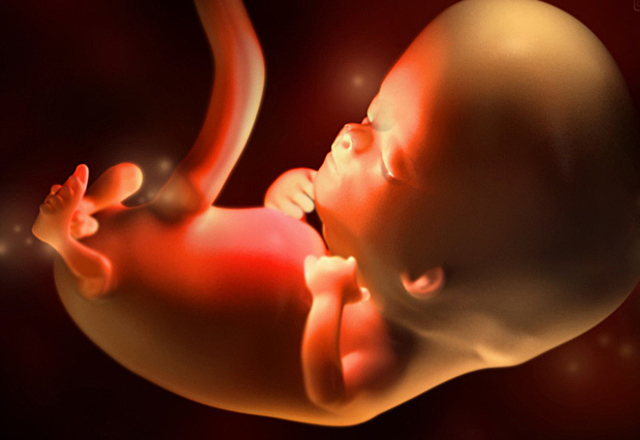

Desarrollo en el embarazo.

Se hacen visibles las yemas de brazos, la placa de la mano y la extremidad inferior en forma de pala. El cerebro se transforma en cinco áreas y algunos nervios craneales son visibles.Alrededor de esta semana, el embrión se convierte en feto, en esta fase, los tejidos y órganos formados durante el periodo embrionario comienzan a madurar, el esqueleto comienza a tomar forma, al igual que el cordón umbilical comienza a ensancharse.

Alrededor de esta semana, el embrión se convierte en feto, en esta fase, los tejidos y órganos formados durante el periodo embrionario comienzan a madurar, el esqueleto comienza a tomar forma, al igual que el cordón umbilical comienza a ensancharse.

Mide entre 13 y 19 mm, los oídos, los dedos y la médula espinal se pueden observar, y las vértebras y costillas comienzan a desarrollarse. Se inicia el crecimiento de todos los músculos del cuerpo.